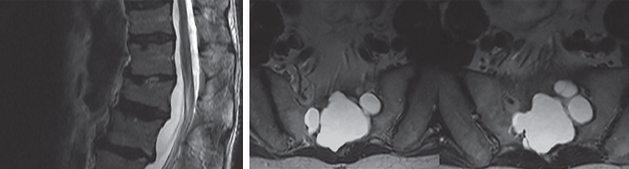

tarlov cyst

04/23/2015

Samia Holman, MSN, FNP-C; Michael J. Kim, MD; Farrukh Merchant, MD, MHSA

A 66-year-old man with history of chronic low back pain presents with worsening pain and right-sided sciatic symptoms. Symptoms were partially relieved by anti-inflammatories, muscle relaxers, and...